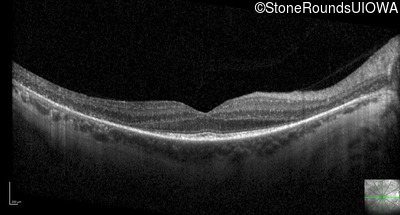

Optical Coherence Tomography - Right - 20/25 -1

Exemplar / OCT Stack

OCT Stack